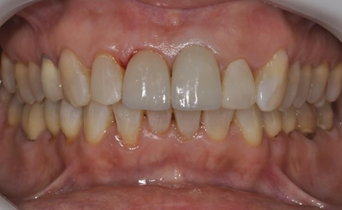

After complete polymerization of the cement, occlusion was checked with the aid of occlusal carbons and the cervical margins were cleaned with an exploratory probe. The cementation interface was finished and polished with abrasive rubbers of different granulations (Figure 12, 13 and 14).

Figure 12 Final aspect of the cemented restorations.

Figure 13 Final aspect of the cemented restorations.

Figure 14 Final aspect of the cemented restorations.